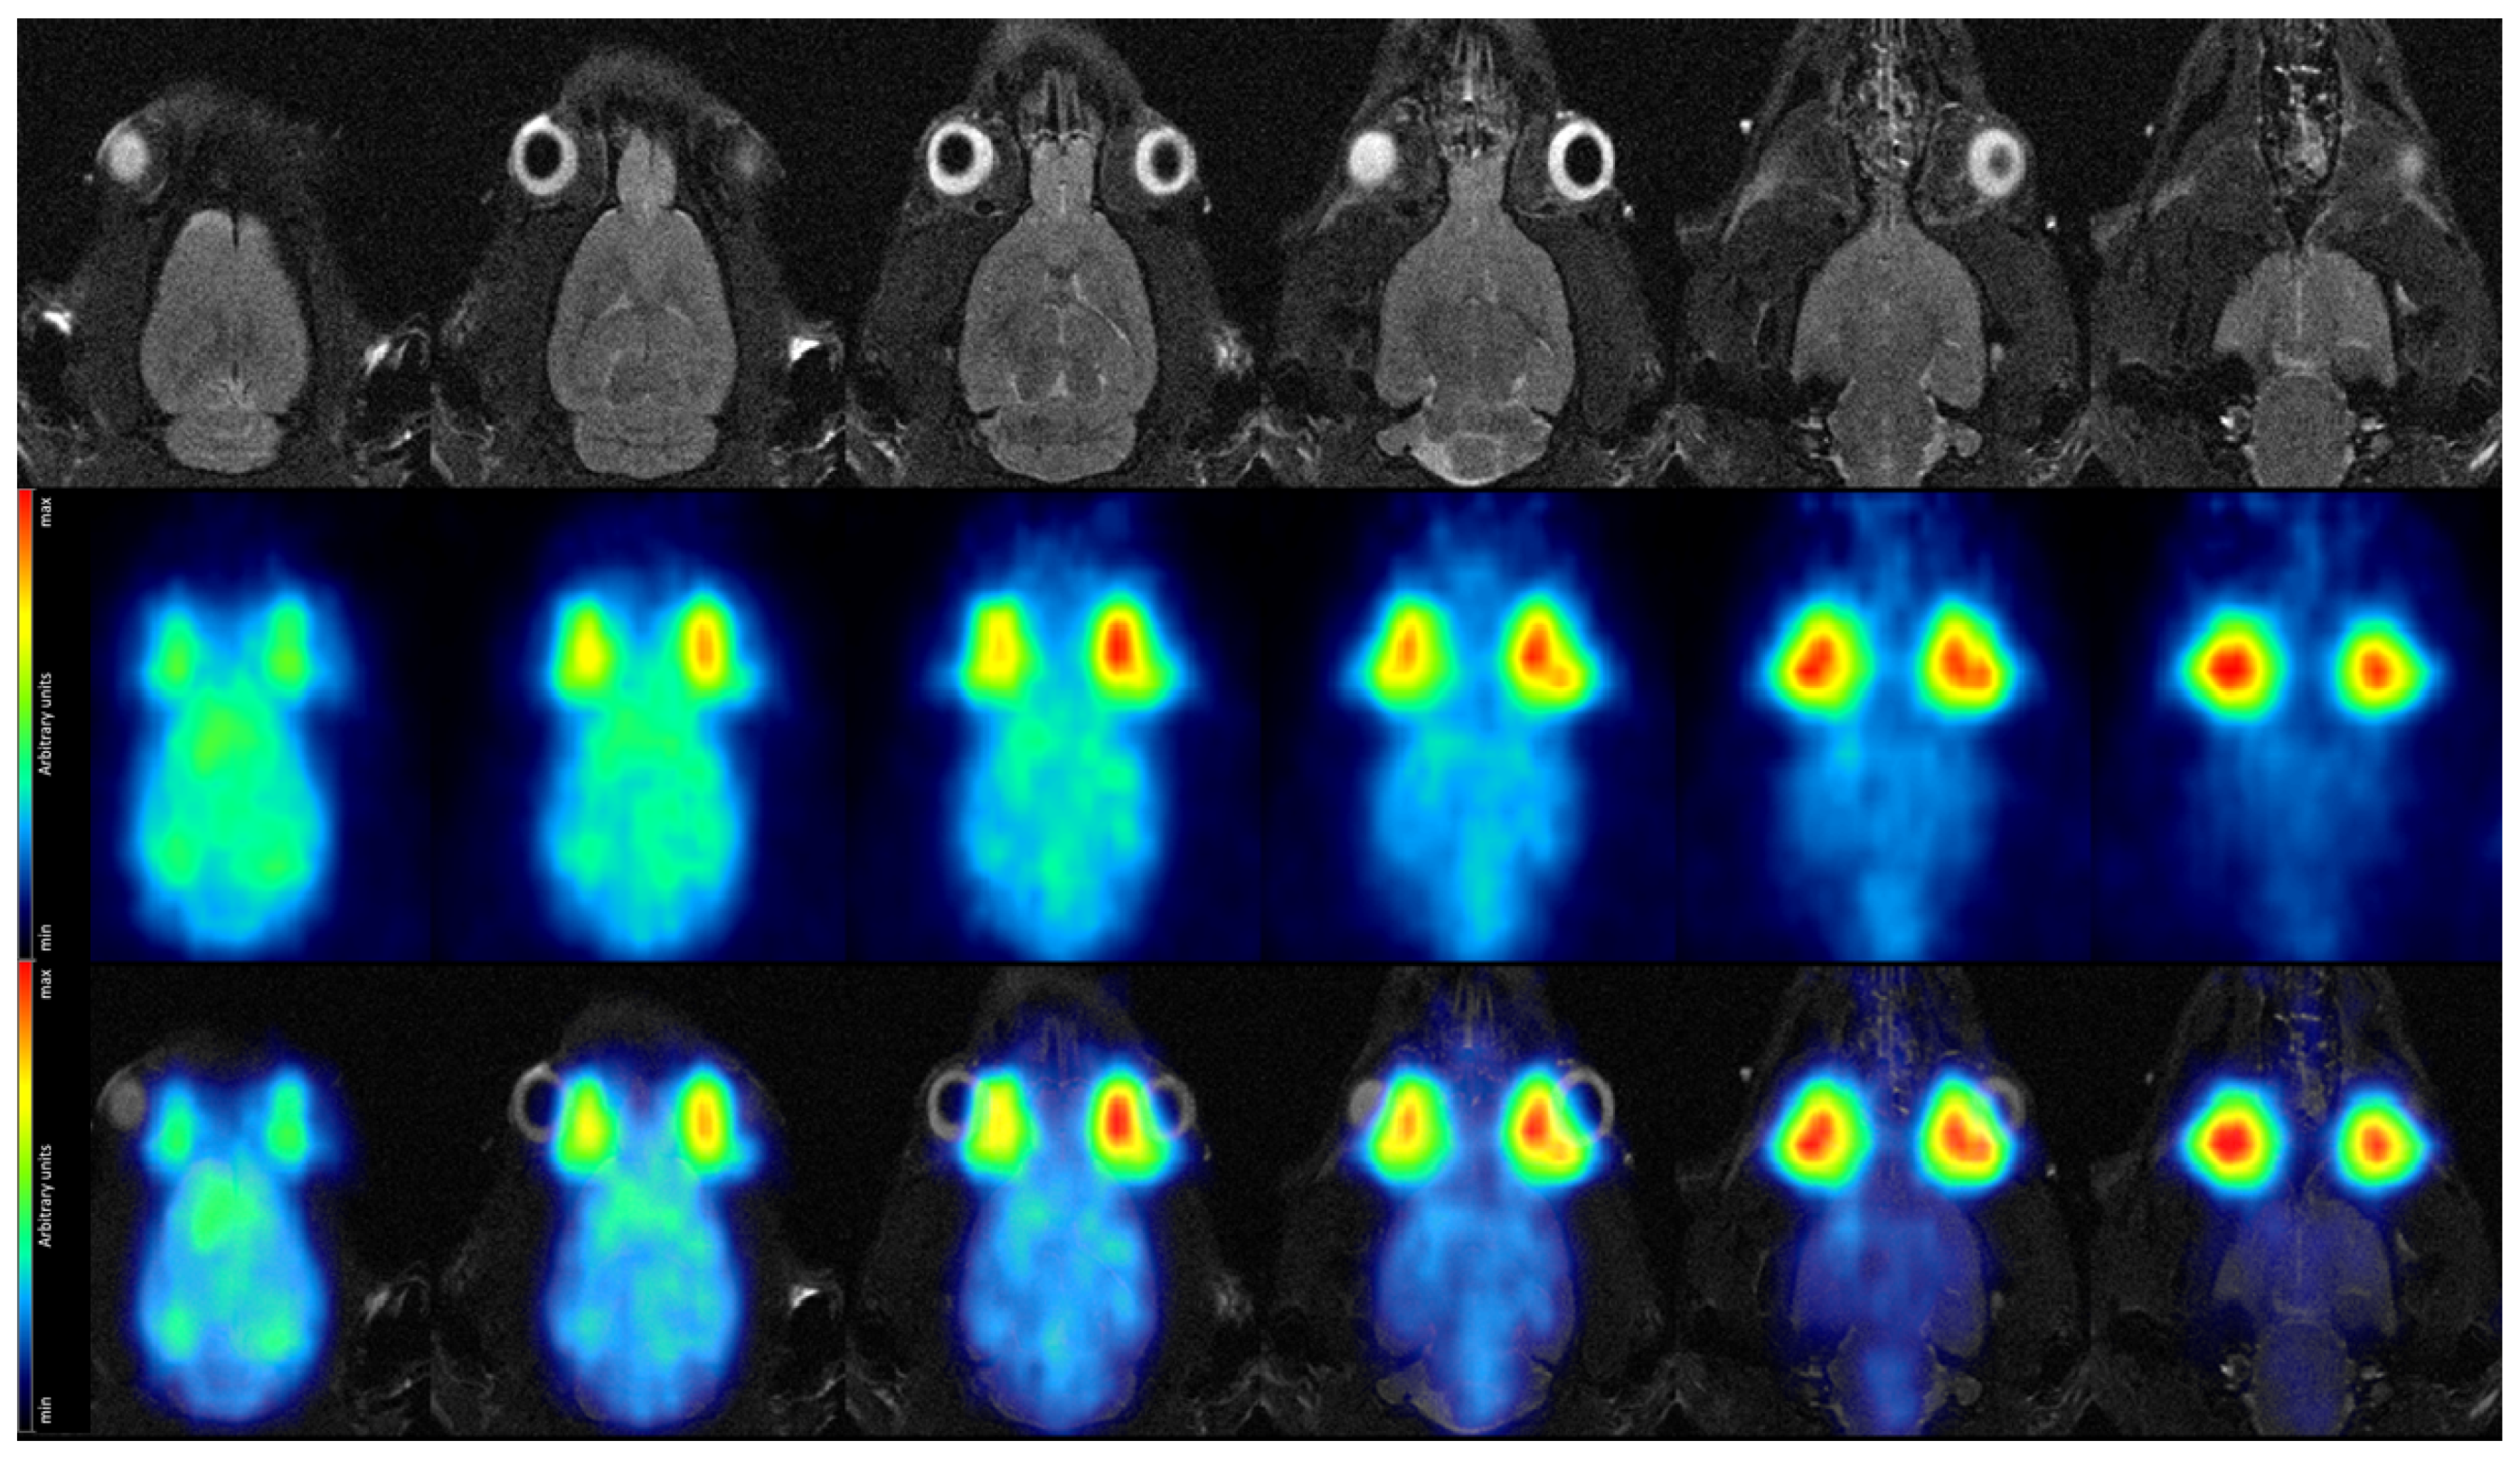

Similarly, we depict the PET image obtained from the 5 time frame at high decay rate in Figure 15, again showing the T2-TurboRARE MR image and the fusion between the two in addition.

Figure 15.

Coronal view of the rat brain in vivo. (Top row): MR images acquired with a T2-TurboRARE sequence. (Middle row): PET data acquired at high decay rate in a single 5 time frame, recorded 44 after tracer injection. (Bottom row): Fused MRI and high-rate PET data.

The image reconstructed from a single 5 time frame out of the high-rate imaging block (Figure 15) gives a first indication on image quality at high acquisition speed, while finer details are partially obscured, more prominent structures are still discernible. The cortex, although less clearly delineated, is still recognizable in most slices, particularly with the MR image at hand providing anatomical reference. However, SAFIR-I’s true high-speed acquisition capability will become apparent only when calculating TACs, where it could enable us to show the rising edge of a TAC with unprecedented temporal resolution.

Regarding the MR images depicted in Figure 14 and Figure 15, it’s worth mentioning that the image quality was not optimal; this was not caused by SAFIR-I but by a small (∼1–2 cm), inadvertent axial offset between the rat’s head and the center of the MRI system in this measurement.